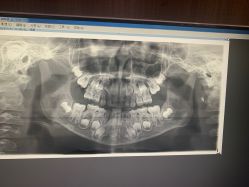

• 睿宝儿科·眼科·口腔(静安大悦城门诊部)

• -睿宝儿科·眼科·口腔(静安大悦城门诊部)

相册

命好的小猫咪 上传于 20-07-20 | 报错